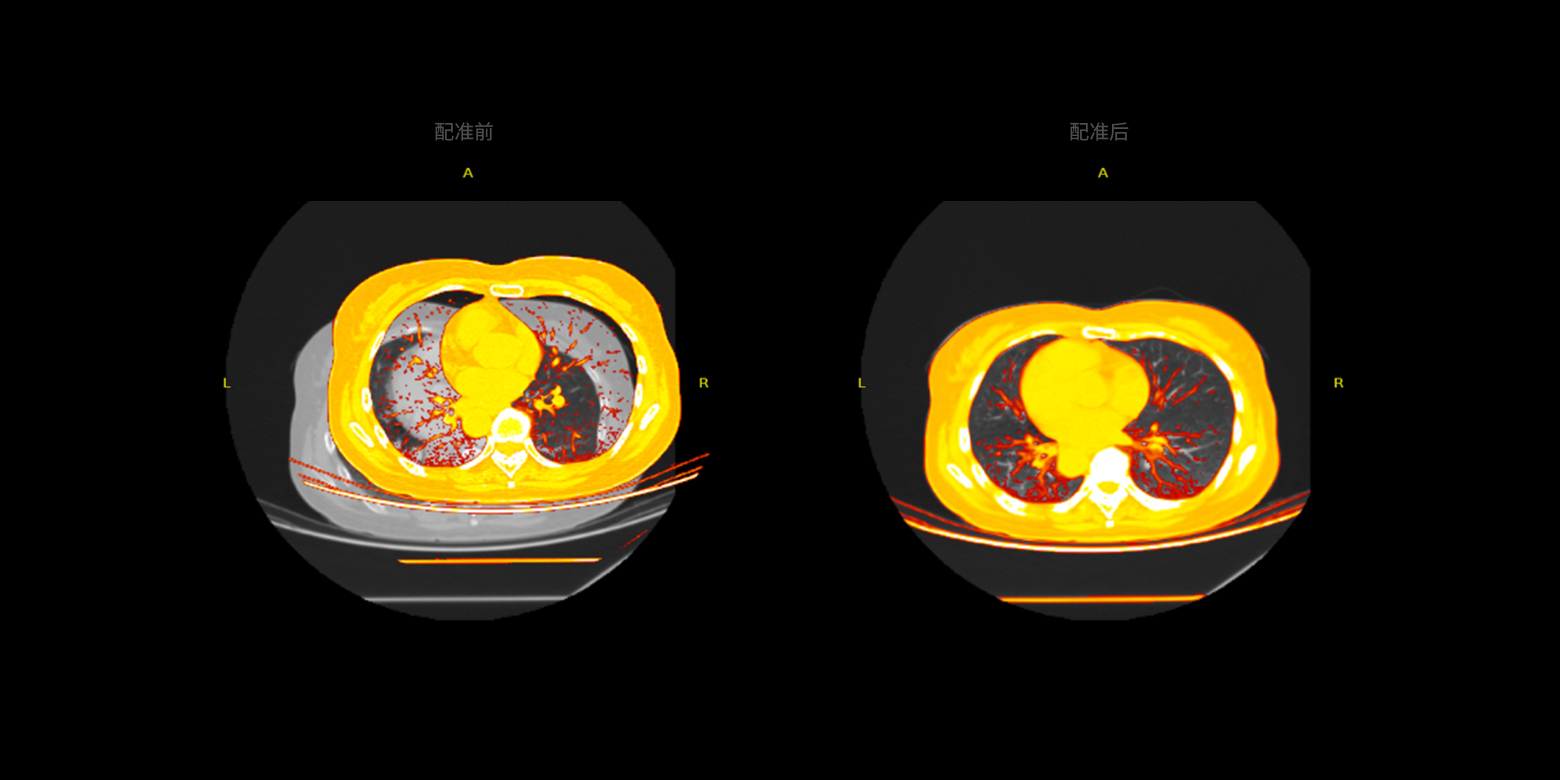

多模态数据的配准

支持同一部位或器官的 CT、MRI、PET 等多模态数据的配准,实现不同模态或不同序列数据之间精确的图像融合,从而能够更精准地对病灶进行定性分级或定量分析。

多模态数据的配准

支持同一部位或器官的 CT、MRI、PET 等多模态数据的配准,实现不同模态或不同序列数据之间精确的图像融合,从而能够更精准地对病灶进行定性分级或定量分析。